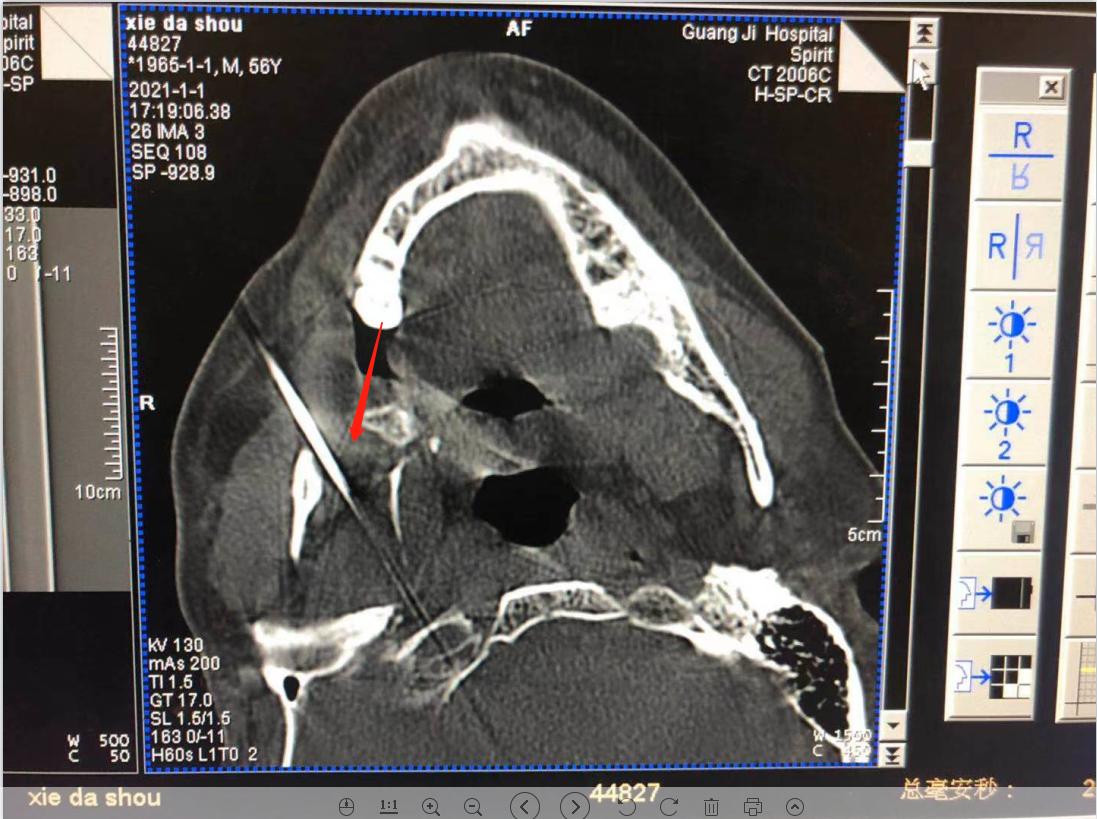

疼痛来得快,也去得快。缓过劲来的刘大伯到附近医院去看医生,被诊断为三叉神经痛,医生为他开了药。早期还有些效果,疼痛很快就能缓解,渐渐地,疼痛变得如影随形,不经意间便又冒出来,说话、吃饭、洗脸、刷牙等生活中常见的行为均可诱发疼痛。 无奈之下,饱受疼痛折磨的刘大伯去了芜湖的多家医院求治,疼痛科、神经内科就诊,基本上都是进行药物治疗,疼痛时好时坏。由于长期大剂量服药,药物治疗的副作用越发显现,这让他苦不堪言,严重影响了他的生活质量。 02不到20分钟的微创手术,彻底解除疼痛烦恼 最近,刘大伯的疼痛发作更频繁了,一吃东西就痛,痛起来更是痛不欲生,根本吃不了东西,被折磨得有气无力。 刘大伯慕名来到我院疼痛科就诊。疼痛科的秦学智主任了解了刘大伯的病情后,秦主任根据他的病史和身体情况,与团队进行了缜密分析和探讨,决定为其实施球囊压迫术解除三叉神经痛。 经秦主任详细解释后,刘大伯和家人欣然同意接受手术。 微球囊压迫术 微球囊压迫术被称为“针尖内的手术”,整个创口仅一个针眼大小,操作时间短,此次手术在局部麻醉下进行,患者全程为清醒状态,此手术具有创伤小、风险小、见效快、恢复快、复发率低的优点。 术中定位进针球囊进入

术中定位

进针

球囊进入